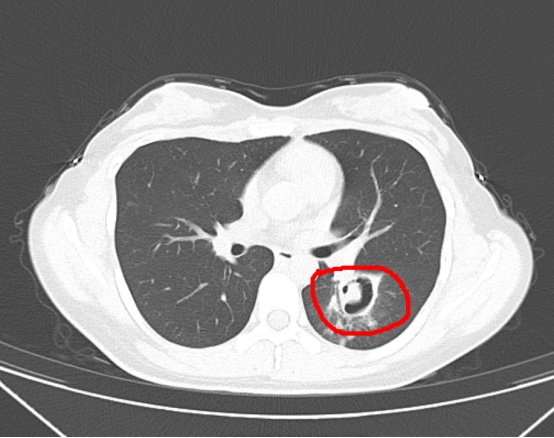

经过一系列检查,医生从肺部CT上发现,王小姐的肺部长出了一个个“小树芽”,怀疑是霉菌性肺炎。接下来,医生对她进行了纤维支气管镜检查,结果发现气道壁上缀着大量白色菌斑,经过化验,确认是曲霉菌。